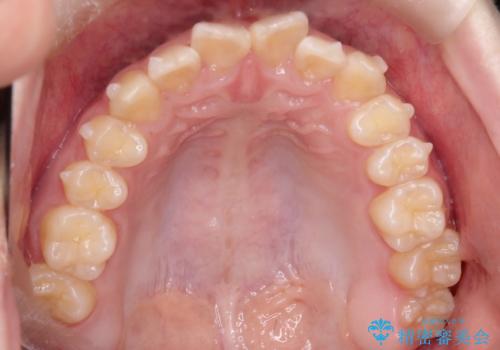

上下の前歯のガタガタを目立たず治したい インビザラインによる見えない矯正

- 上下の前歯のガタガタを治したいとのことで来院されました。

上下の歯と歯の間をわずかに削り、並べる計画としました。